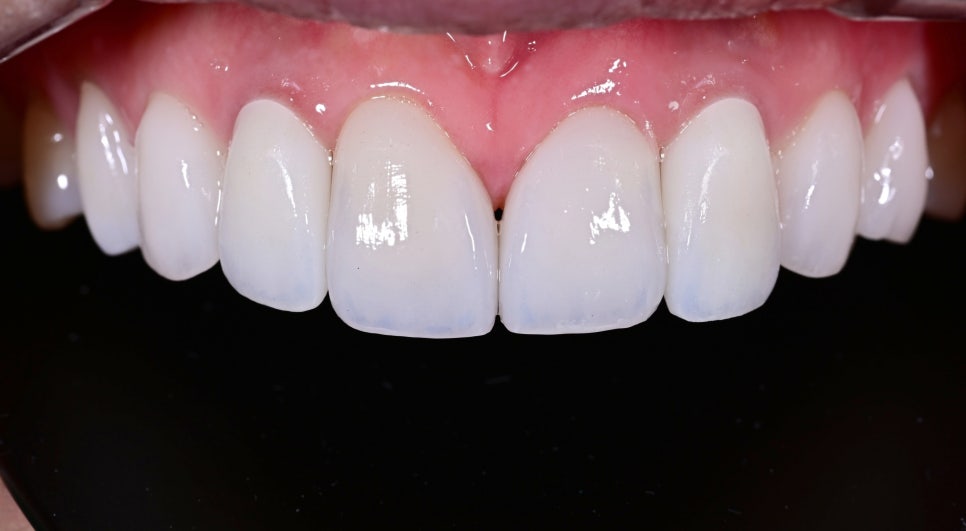

치료 후 변화

치료 후 가장 큰 변화는 “더 이상 임플란트가 따로 놀지 않는다”는 점이었습니다.

기존에는 임플란트 부위가 주변 치아와 미묘하게 다르게 보여 앞니 전체의 통일감을 해치고 있었지만, 치료 후에는 앞니의 색감과 형태, 비율이 훨씬 부드럽게 연결되면서 전체 인상이 한층 정돈되고 자연스러워졌습니다.

또한 너무 차갑거나 인위적인 흰색이 아니라 환자분 이미지에 어울리는 깨끗하고 고급스러운 화이트 톤으로 완성되어 웃을 때의 분위기 자체가 훨씬 밝아졌습니다.